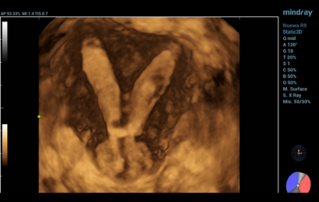

Female pelvic floor anatomy, which developed since the early 20th century, has had a variety of theories, including integral theory, three levels of vaginal support theory, "hammock hypothesis", and three-chamber system. Supporting structures such as pelvic floor muscles, fascia and ligament play an important role in maintaining the normal function of pelvic floor, among which levator ani muscle group is one of the most important supporting structures.